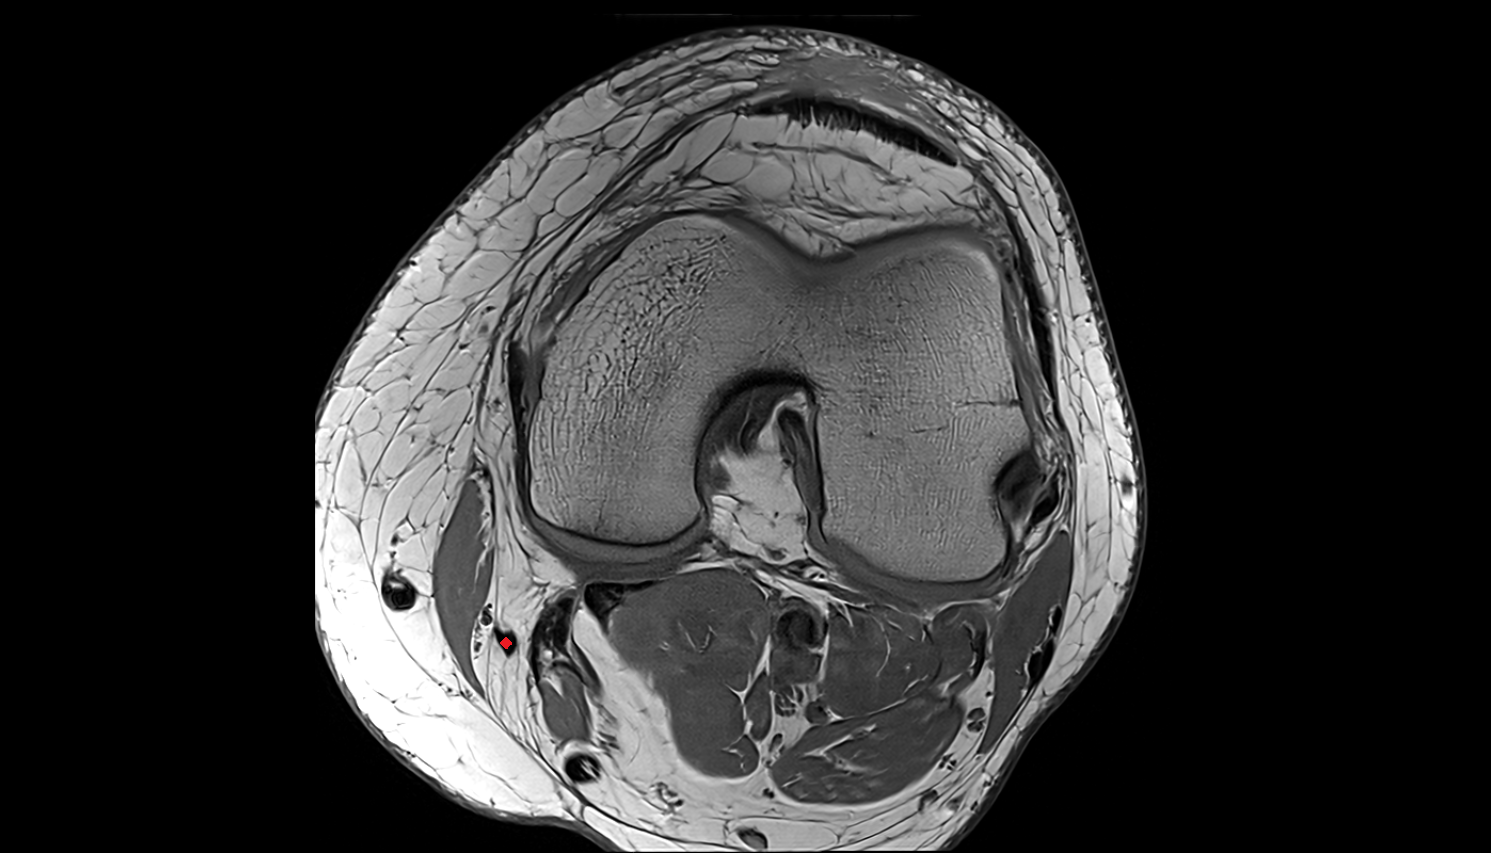

- Knee Joint